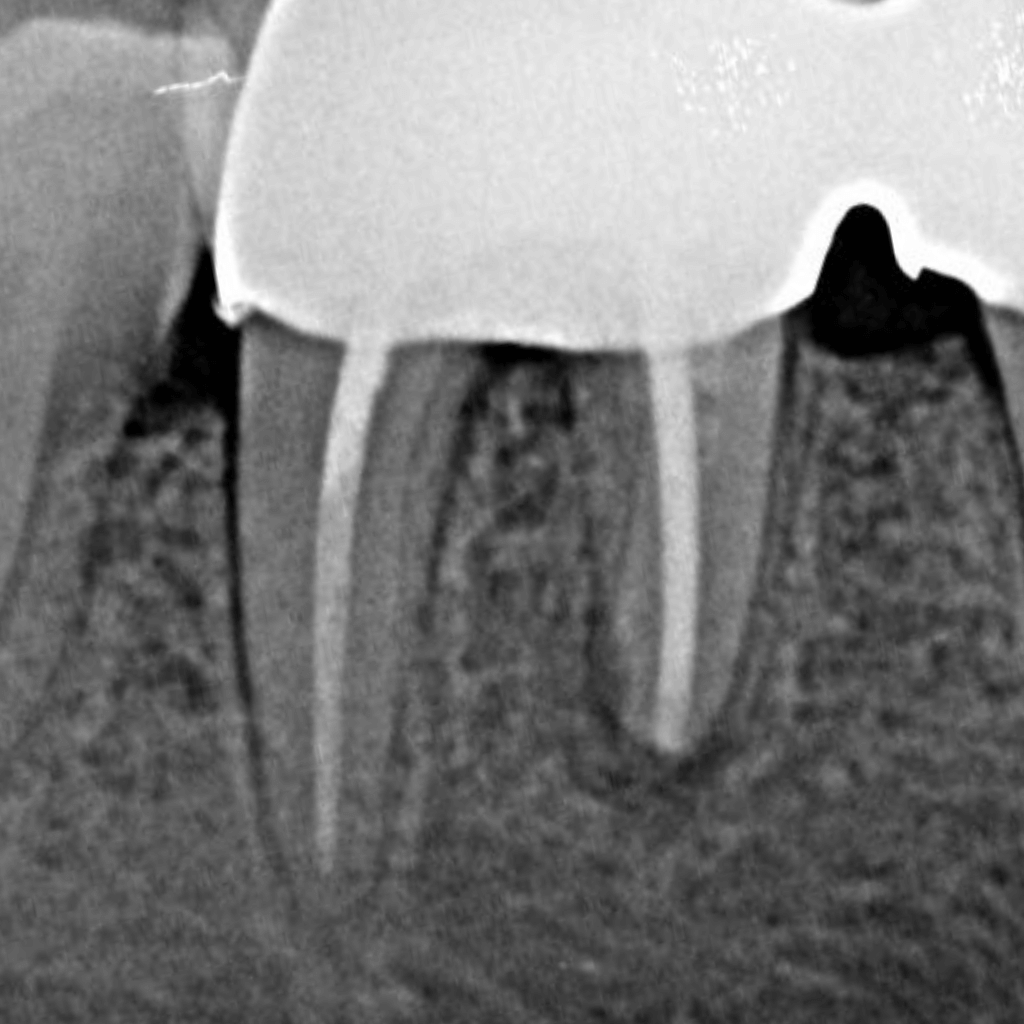

Оценяваме състоянието на зъба и кореновата система чрез клиничен преглед и образна диагностика, за да планираме лечението прецизно.

Инфектираните тъкани се отстраняват внимателно, а каналите се обработват механично и ръчно, с цел пълно почистване.

Каналите се дезинфекцират и оформят така, че да бъдат подготвени за надеждно запълване.

Кореновите канали се запълват херметично с биосъвместим материал, който предотвратява повторна инфекция.